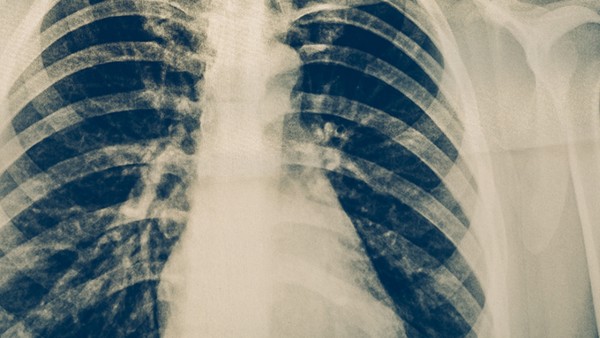

5、X线检查:是初中入学肺结核筛查的常规检查方法,能够直接判断肺部是否发生病变,明确病变位置、形态、密度、周围组织异常变化等,在一定程度上还可以判断病变的性质。